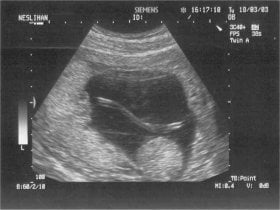

12 haftalık gebelikte umbilikal kordonun

ultrasonografik görüntüsü